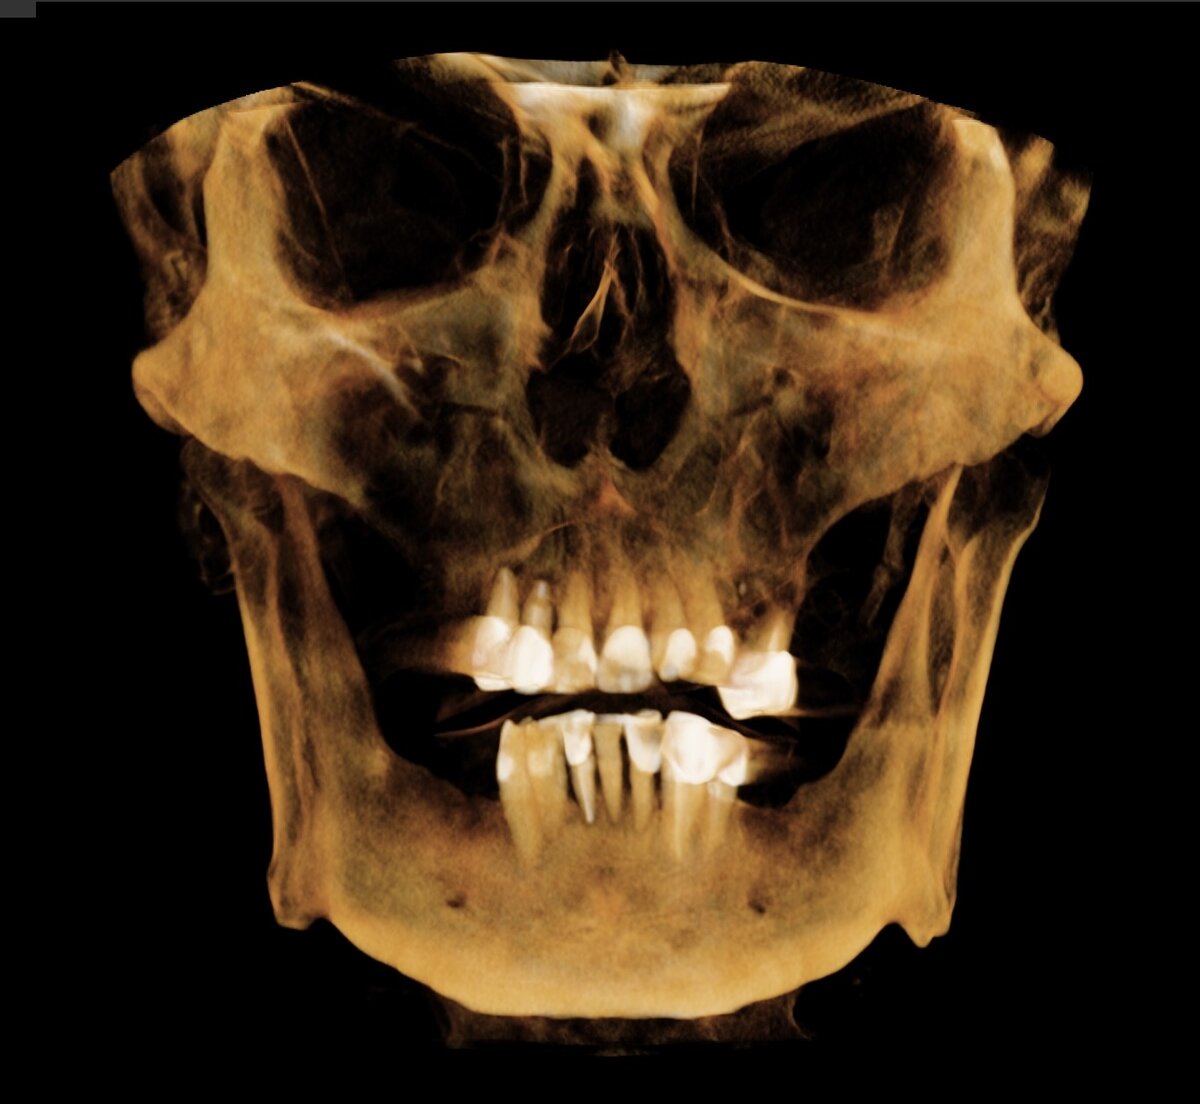

По снимку КЛКТ видим вот какую картину:

Цифровая визуализация

Зубы сохранились только во фронтальных отделах верхней и нижней челюсти. Состояние этих зубов печальное. Оголение корней до 2/3 длины, визуализируются очаги деструкции костной ткани в области верхушек корней ("кисты" в народе). Сами корни под коронками поражены кариозным процессом.

Оцениваем состояние кости. На нижней челюсти всё ок, без проблем реализуемо. Сверху же кости не хватает в области пазух. В левой пазухе сюрприз - она на 1/2 заполнена чем-то.